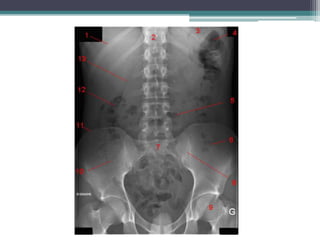

Tài liệu bàn về tắc ruột, bao gồm định nghĩa, phân loại và nguyên nhân của tình trạng này, với sự phân biệt giữa tắc cơ học và cơ năng. Các triệu chứng và chẩn đoán lâm sàng được trình bày, kèm theo phương pháp chẩn đoán cận lâm sàng như x-quang và siêu âm. Ngoài ra, tài liệu cũng đề cập đến các biến chứng và hậu quả của tắc ruột.